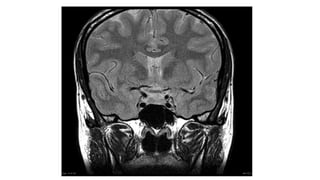

A coronal T2 weighted image shows a low T2 signal adenoma in

the left side of the gland (arrow) which represented a densely

granulated GH secreting adenoma.

T2 • Standard sequence •Fluid is bright (hyper-intense) • White matter is darker than grey

A coronal T2weighted image shows a low T2 signal adenoma in the left side of the gland (arrow) which represented a densely granulated GH secreting adenoma.